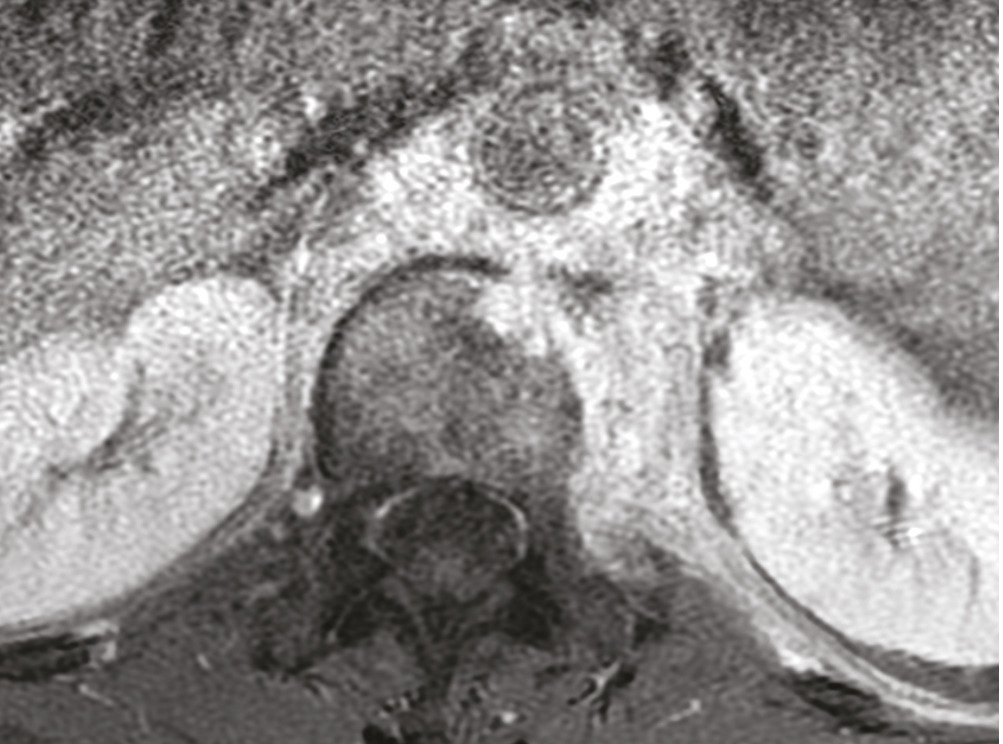

Cet homme de 53 ans consultait pour une douleur de la charnière dorsolombaire à irradiation antérieure, mal calmée par les antalgiques, avec un amaigrissement sans fièvre. L’examen clinique trouvait une raideur rachidienne et le bilan biologique montrait un syndrome inflammatoire. La tomodensitométrie (TDM) abdominale révélait une fibrose rétropéritonéale avec lyse de L1 (fig. 1 ). L’imagerie par résonance magnétique (IRM) montrait un aspect de fibrose rétropéritonéale secondaire, en hyposignal T1 et T2, se rehaussant après injection du gadolinium avec lyse de L1 (fig. 2 ). La tomographie par émission de positons au 18-fluorodésoxyglucose (TEP18-FDG) montrait un hypermétabolisme intense de L1 dont la biopsie scannoguidée révélait un granulome épithélio-giganto-cellulaire cadrant avec une tuberculose (fig. 3 ). Le patient était efficacement traité par les antibacillaires pendant 9 mois.

La fibrose rétropéritonéale est caractérisée par la présence d’un tissu fibro-inflammatoire aberrant engainant les gros vaisseaux et les uretères. À côté de la forme idiopathique, il existe des formes secondaires à des médicaments, à un anévrisme de l’aorte, à un cancer et aux infections.1 La biopsie est indiquée devant l’existence d’un tissu anormal entre l’aorte et les vertèbres avec déplacement antérieur des gros vaisseaux ou d’un en- vahissement des structures adjacentes.1 La TEP18-FDG per-met de déceler la présence d’un processus cancéreux ou infectieux accessible à la biopsie.1 La fibrose rétropéritonéale secondaire à la tuberculose est rare, les sites rapportés de tuberculose sont : le rachis, le rein et les ganglions.2 Les mécanismes de genèse de la fibrose pourraient être en rapport avec l’auto-immunité provoquée par la tuberculose.2